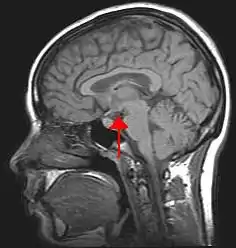

The hypothalamus (pl.: hypothalami; from Ancient Greek ὑπό (hupó) 'under', and θάλαμος (thálamos) 'bed') is a small part of the brain that contains a number of nuclei with a variety of functions. One of the most important functions is to link the nervous system to the endocrine system via the pituitary gland. The hypothalamus is located below the thalamus and is part of the limbic system.[1] It forms the ventral part of the diencephalon. All vertebrate brains contain a hypothalamus.[2] In humans, it is the size of an almond.

Location of the hypothalamus